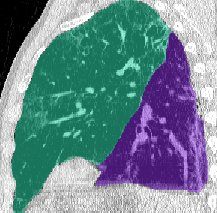

Lung segmentation results for the polymorphic and nonpolymorphic models are shown in Figure 3. Quantitative evaluation of lung segmentations was performed on CT images by comparing the segmentations to ground truth manual segmentations. The Dice coefficient was used to measure volume overlap and the average symmetric surface distance (ASSD) was used to assess boundary accuracy. The ASSD and Dice coefficient results for each of the four evaluation datasets are shown in Table 2. Overall, on the COVID-19 dataset the polymorphic model achieved an average ASSD of mm and average Dice coefficient of . By comparison, the nonpolymorphic model achieved an average ASSD of mm and average Dice coefficient of . ASSD and Dice coefficient results with respect to nonaerated lung volume fraction are displayed in Figure 4. Two-way analysis of variance revealed a significant interaction between model and nonaerated fraction for each evaluation metric, indicating that the regression coefficients with respect to nonaerated fraction were significantly different for polymorphic vs. nonpolymorphic models.

Lobar Segmentation

Lobar segmentation results for the proposed method and PTK are shown in Figure 5 for right lungs and Figure 6 for left lungs. For each image in the COVID-19 dataset (133 images in total), the lobar segmentation result was used to extract the amount of poor aeration () and consolidation () in each lobe. Common phenotypes of COVID-19 affected lungs were identified by hierarchical clustering over the fraction of poorly aerated and consolidated tissue in each lobe. Dendrographic analysis in Figure 7 reveals four primary clusters of patients that were identified by the hierarchical clustering: (a) mild loss of aeration primarily in the two lower lobes without consolidation; (b) moderate loss of aeration focused in the two lower lobes with or without consolidation in lower lobes; (c) severe loss of aeration throughout all lobes with or without consolidation; and (d) severe loss of aeration and consolidation throughout all lobes.